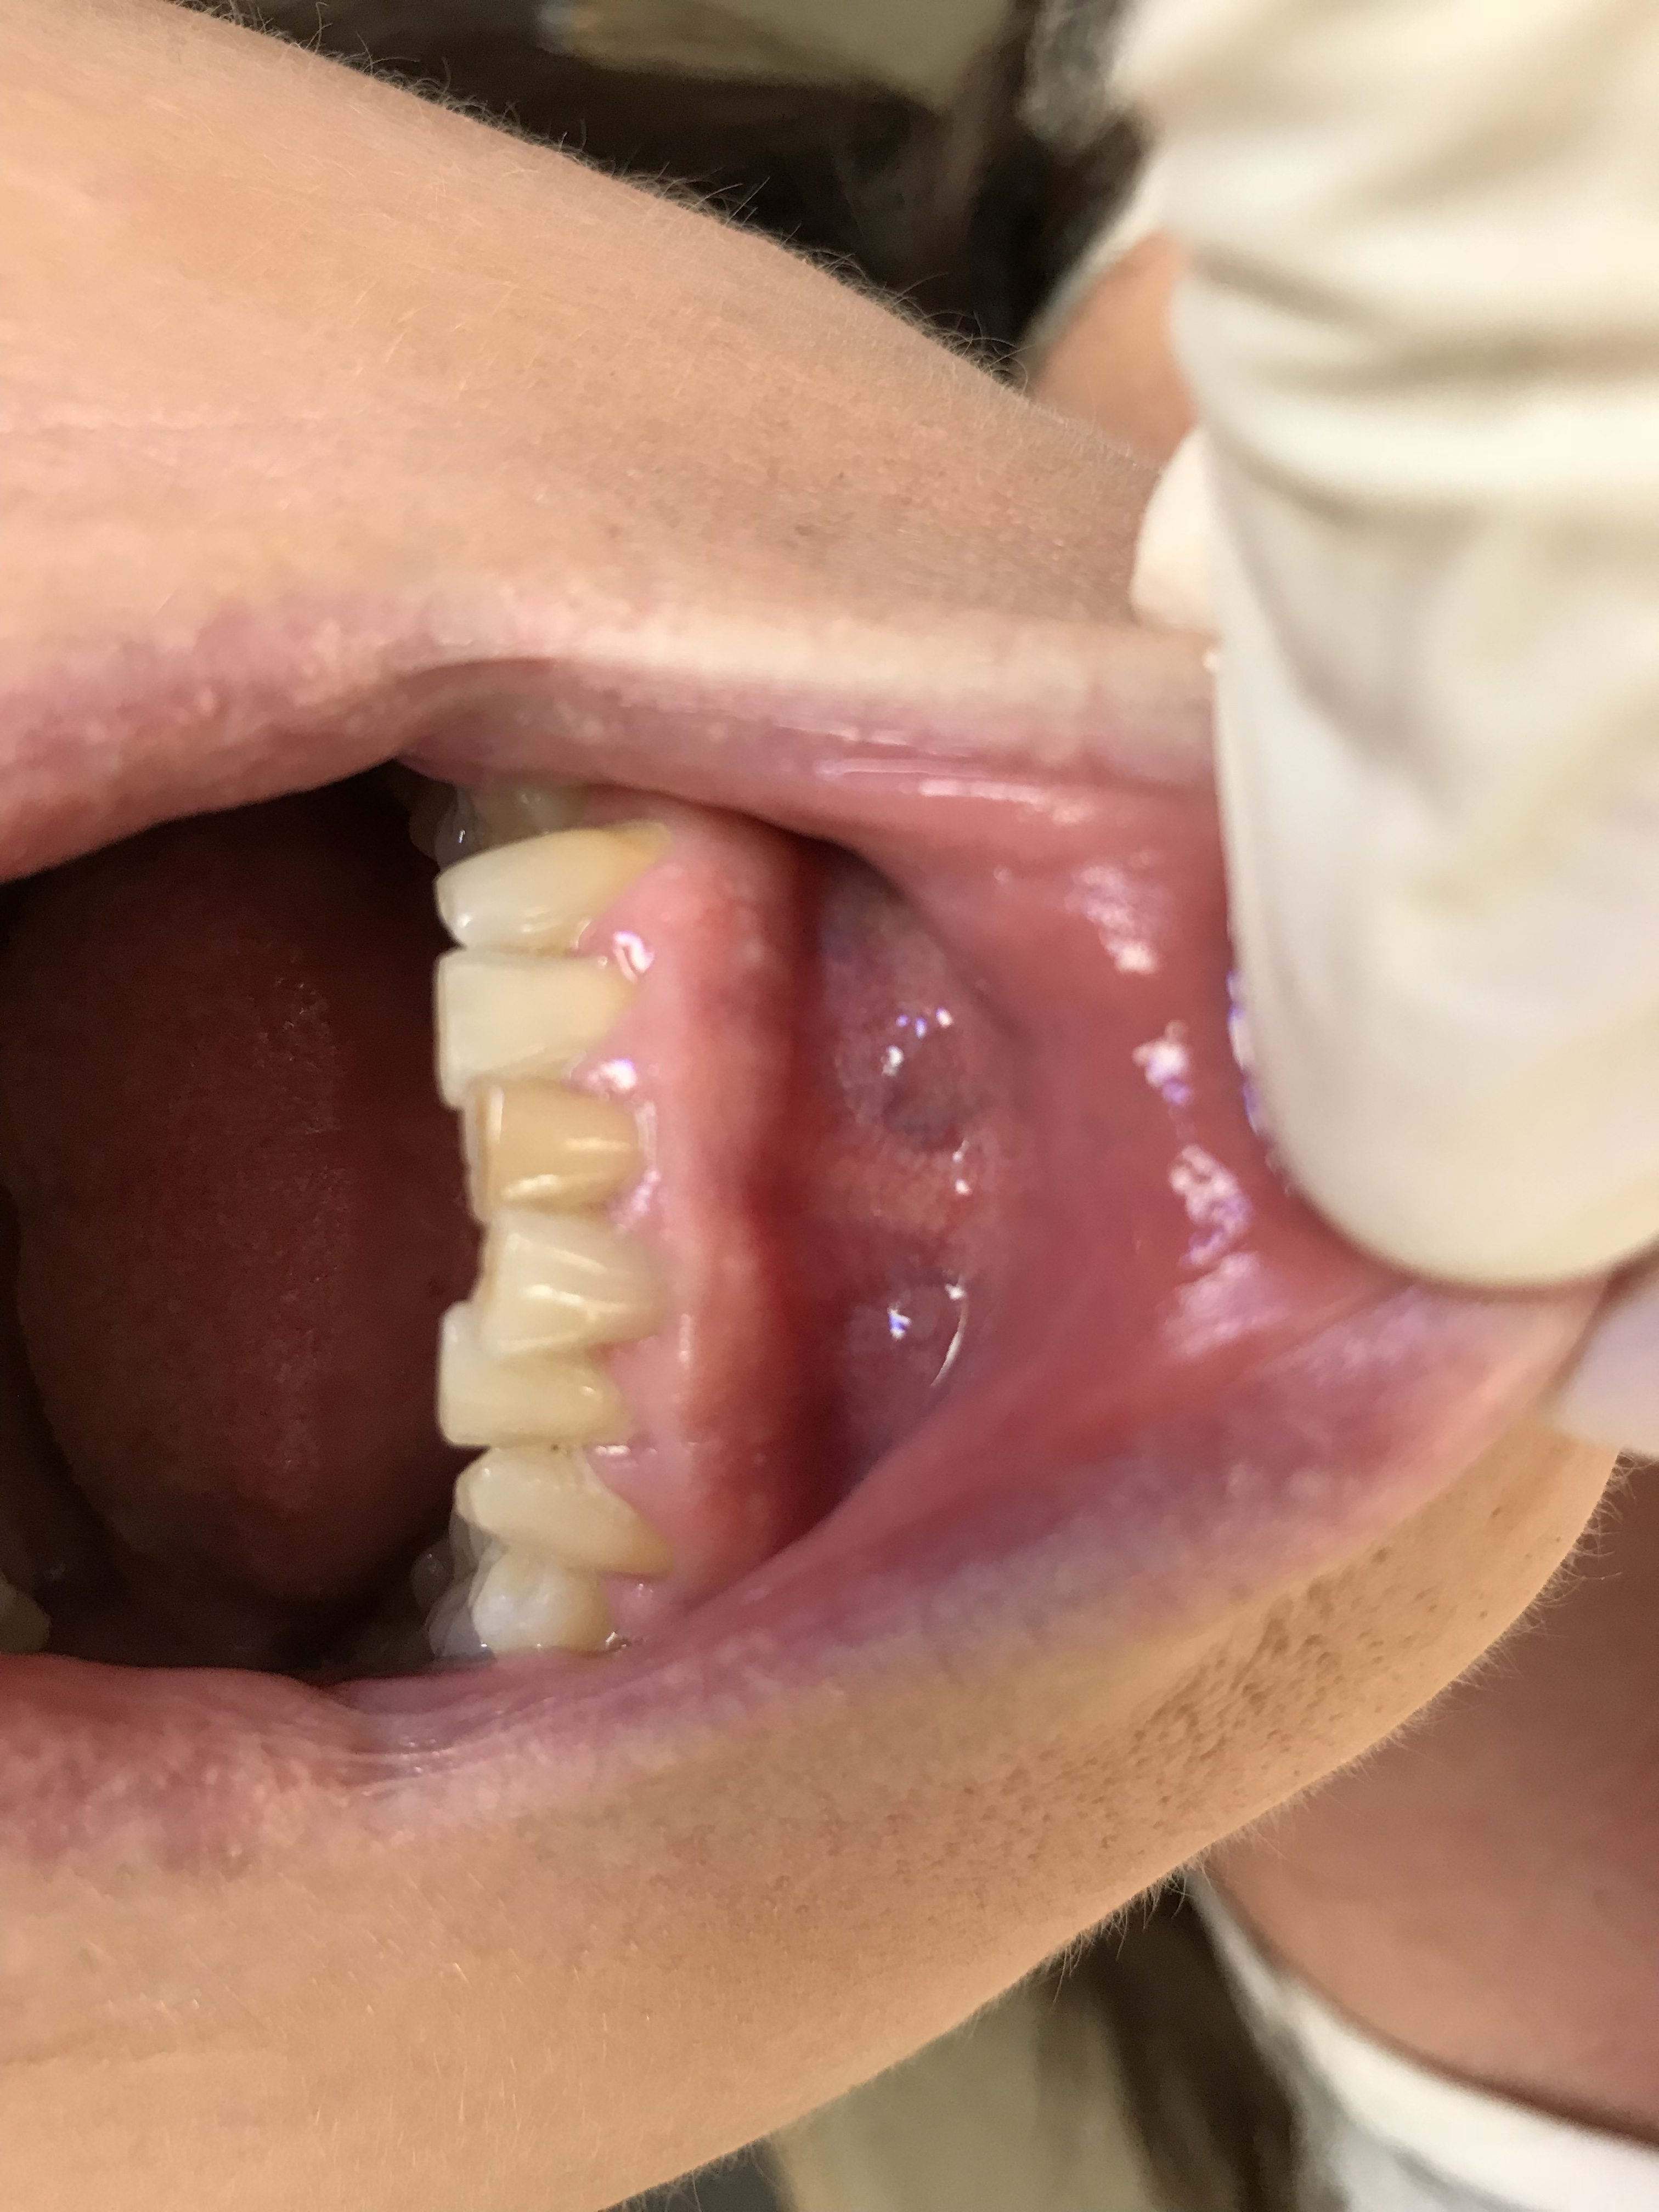

Vraiment on se demande d’où bien peuvent venir ces jaunissements . C’est vraiment un mystère . Et pourtant elle a une sensibilité au froid . Quelle surprise ! What a surprise ! En anglais dans le texte ....

B74b731e 4672 4504 a1f8 3ef25e40bd5f zte6ze - Eugenol